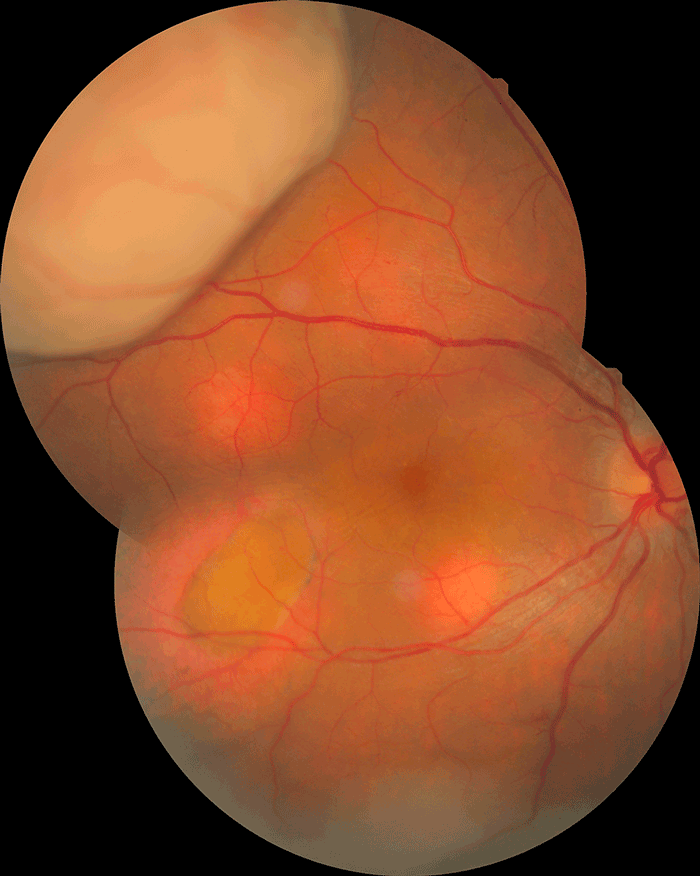

Rétinoblastome Diagnostic du rétinoblastome Le rétinoblastome est une tumeur intraoculaire maligne de l'enfant dont on recense environ 50-60 nouveaux cas par an en France. L'âge moyen au diagnostic est de 1 à 2 ans selon les formes cliniques. C'est une maladie génétique, liée à la présence de mutations au niveau des deux allèles du gène RB1. L'atteinte peut être uni- ou bilatérale et un contexte familial est retrouvé dans 10 % des cas. L'atteinte est plus souvent bilatérale, multifocale, plus sévère et plus précoce en cas de prédisposition génétique. Le pronostic vital est excellent dans les pays à haut revenus, avec en France une survie supérieure à 99 %. Le pronostic visuel est cependant souvent moins favorable. Les signes d'appel les plus fréquents sont une leucocorie (Figures 12 et 13) et un strabisme. Une leucocorie est un reflet blanc au travers de la pupille parfois transitoire ou visible sur photo. L'évocation par les parents d'une leucocorie ou l'apparition d'un strabisme doit faire évoquer un rétinoblastome, et un fond d'œil doit être réalisé en urgence sous anesthésie générale. Au fond d'œil, on observe une ou plusieurs masses tumorales rétiniennes blanchâtres (Figures 14 et 15), parfois calcifiées, de dimensions variables, pouvant aller d'une lésion inframillimétrique débutante (Figure 16) à une tumeur volumineuse occupant toute la cavité vitréenne (Figure 17). Un décollement de rétine exsudatif, un essaimage tumoral sous-rétinien, intra-vitréen ou en chambre antérieure (Figure 18) peuvent être présents et sont de mauvais pronostic. Une IRM orbitaire doit être réalisée rapidement, pour confirmer le diagnostic et vérifier l'absence d'extension extraoculaire (Figure 19). Le scanner est déconseillé car l'irradiation est mutagène et augmente le risque de tumeurs secondaires en cas de prédisposition génétique. Les enfants en bas âge dans la fratrie devront également bénéficier d'un examen ophtalmologique complet, au besoin sous anesthésie.

Figure 17 Volumineux rétinoblastome diagnostiqué à un stade avancé.